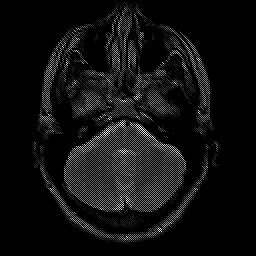

glioma overlay -- Slice #6

[Home][Help][Clinical] Slice 6